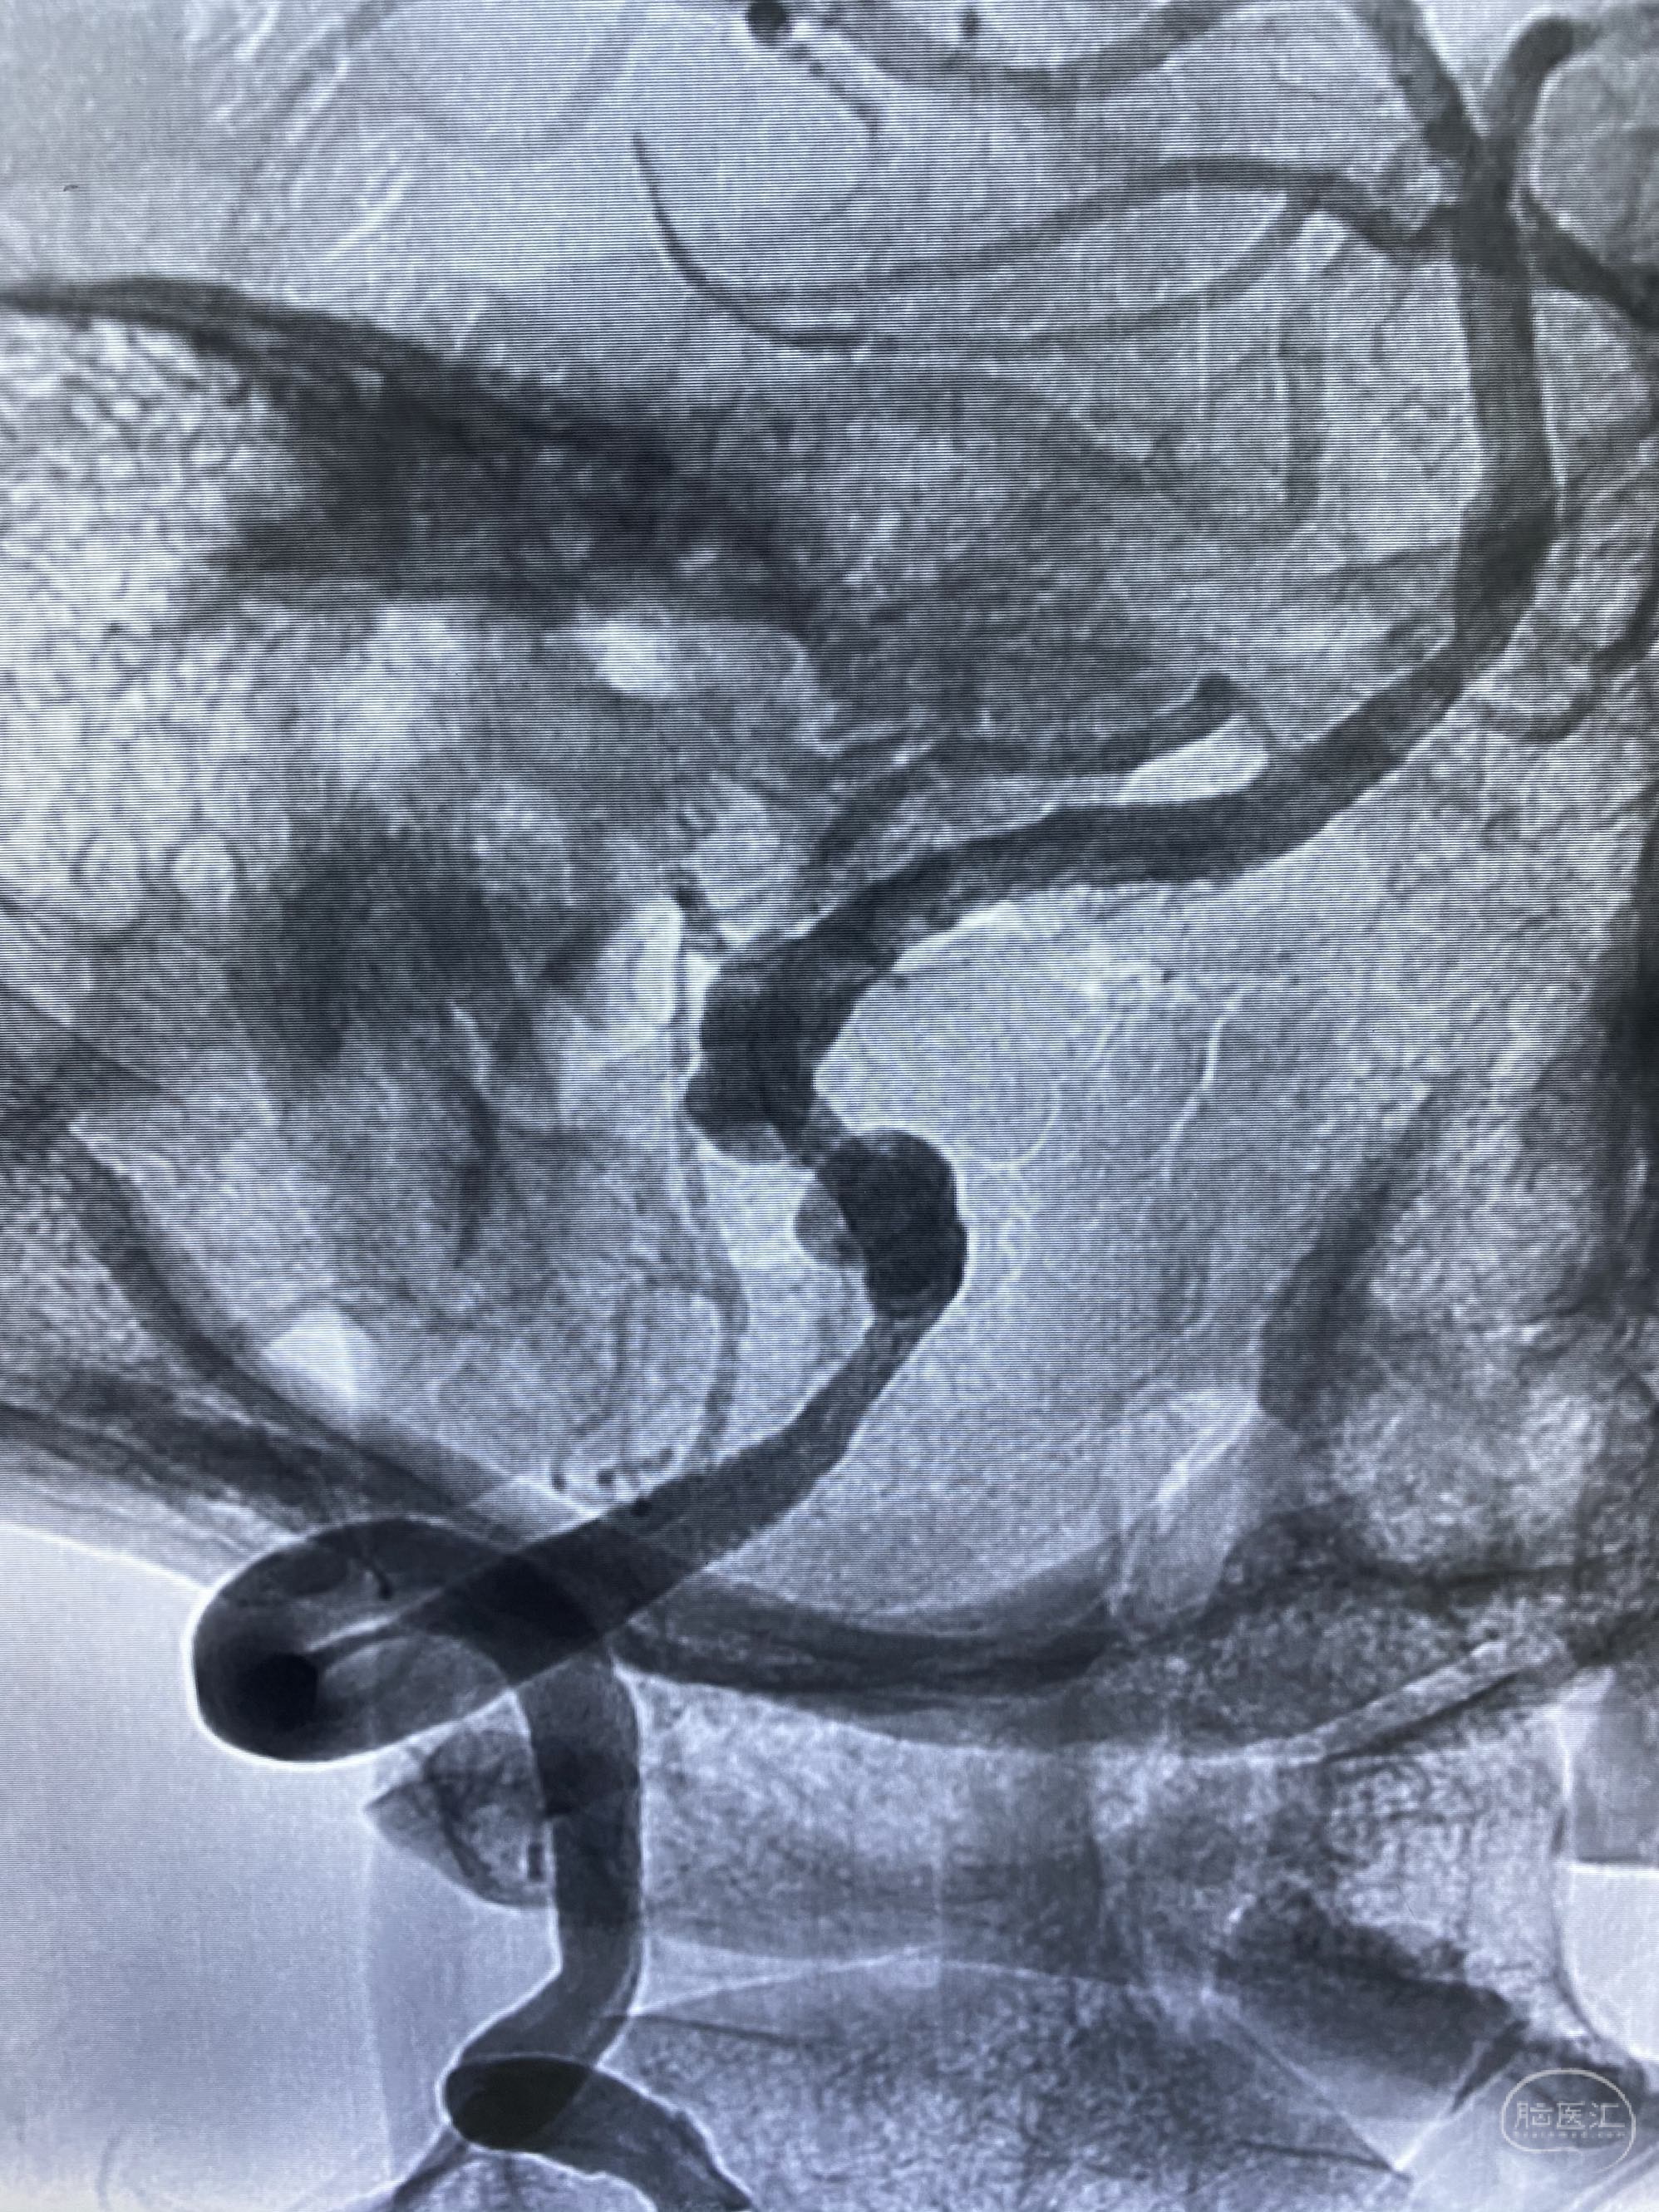

今日手术,TJG,M62Y,一期左侧颈动脉狭窄支架植入,二期椎动脉V4段多发夹层动脉瘤伴狭窄,常规支架辅助栓塞方法复杂又危险,血流导向装置植入快捷又安全。南阳市中心医院神经内科脑血管病介入团队pipeline flexFD植入两人导师资格。

椎动脉颅内段多发夹层动脉瘤伴载瘤动脉狭窄pipeline flex植入

今日手术,TJG,M62Y,一期左侧颈动脉狭窄支架植入,二期椎动脉V4段多发夹层动脉瘤伴狭窄,常规支架辅助栓塞方法复杂又危险,血流导向装置植入快捷又安全。南阳市中心医院神经内科脑血管病介入团队pipeline flexFD植入两人导师资格。